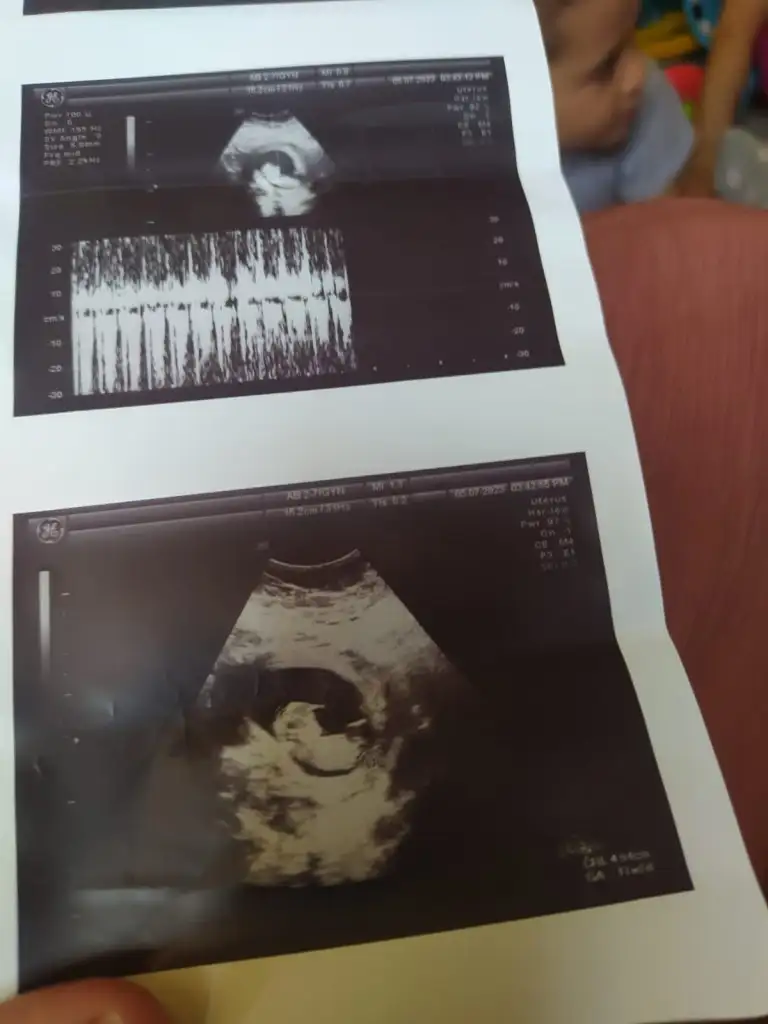

Selam arkadaşlar buraya bir arkadaşmn ultrason fotoğrafları atıyorum bir türlü cinsiyet oğrenemedi çok merak ediyor sizden ricam bir tahminde bulunabilirmsnz soyasosu canm sen anlıyordun dmi

• IMG-20230717-WA0006.webp

IMG-20230717-WA0006.webp

20,9 KB · Görüntüleme: 75

• IMG-20230717-WA0005.webp

IMG-20230717-WA0005.webp

19,6 KB · Görüntüleme: 77

• IMG-20230717-WA0004.webp

IMG-20230717-WA0004.webp

21,7 KB · Görüntüleme: 70